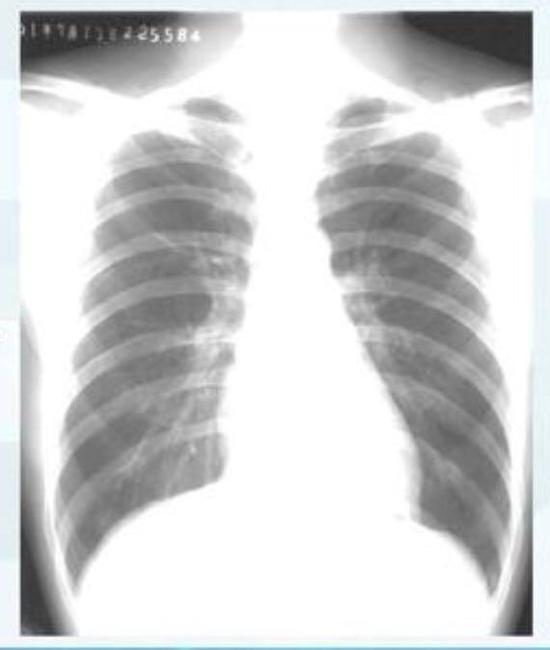

按照國家衛健委發布的新型冠狀病毒肺炎試行第六版診療方案之中的臨床分型,新冠肺炎分為輕型、普通型、重型及危重型。在患者的肺部CT中,輕型者沒有比較明顯的肺炎改變;普通型者以肺部出現局限性斑片狀或很多節段性片狀“病灶”為主(圖②);重型者雙肺可出現較多的白色小斑片“病灶”,部分融合成大片狀“病灶”(圖③);危重型者會有“白肺”表現(圖④)。

▲從上到下依次為普通型、重型及危重型新冠肺炎患者的肺部CT表現(圖片來自網絡)

▲正常情況下人的肺部CT表現(圖片來自網絡)